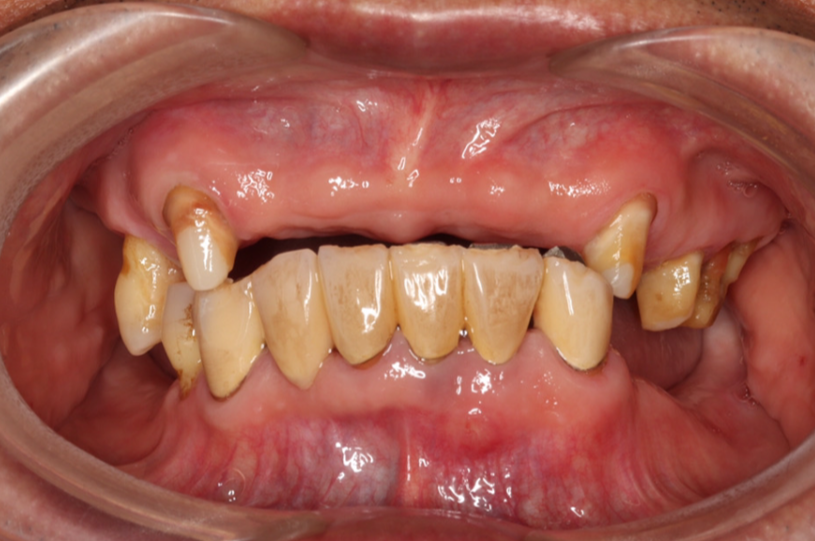

治療前

治療内容 重度の歯周病となり、口腔内全体の抜歯をして、上下の歯をBPS(リハビリあり)デンチャーにしました。

期間

約7か月

費用 1,914,000円(税込)

副作用・リスク 壊れた場合、修理に時間がかかる場合があります。